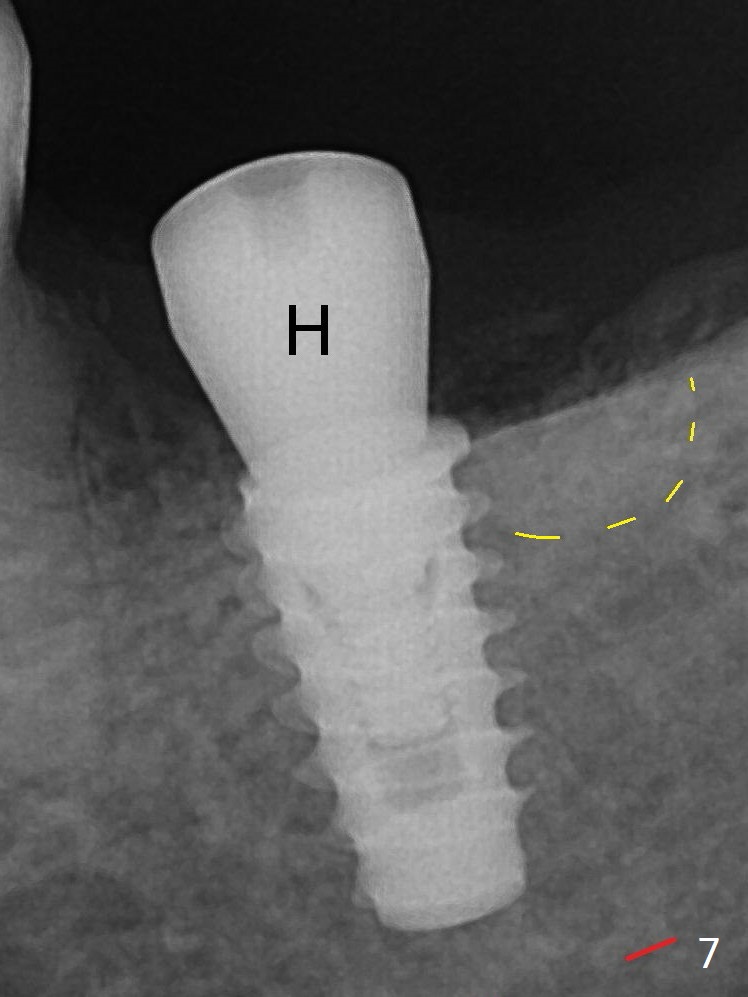

There is chewing pain in spite of previous occlusal adjustment 7 months post cementation (Fig.11-13: increased radiolucency around the implant). The crown/abutment is removed and a healing abutment is placed (6x3 mm); the implant is found to be stable. The patient will return for re-evaluation in 3 months. Check proximal contact after crown reseating. Occlusion should be light, since #18 is the only molar with a natural opposing tooth (heavy occlusion). The patient return for re-evaluation in 3 months (15 months postop); radiolucency appears to reduce (Fig.14). But there is pain when the healing abutment is being removed. After local anesthesia, the implant is removed with a wrench.